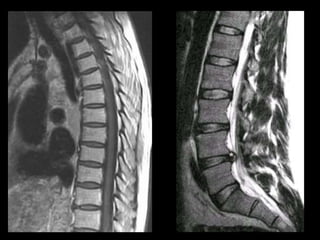

This document provides an overview of normal musculoskeletal imaging. It discusses basic x-ray concepts and densities. It then reviews normal anatomy as seen on x-rays of the skull, spine, pelvis, chest, and extremities. Key anatomical structures are labeled on example x-rays for the shoulder, hip, knee, and foot. Quizzes are included to test recognition of anatomical structures and patient age based on x-rays.